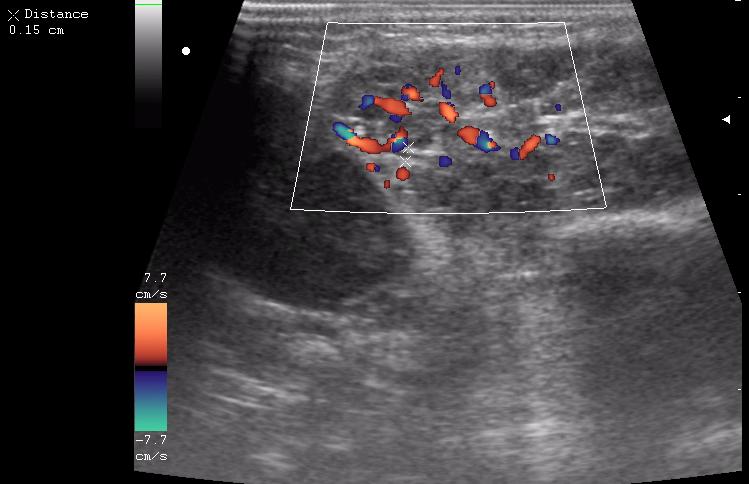

В гнойную хирургию положили ребенка с двусторонним шейным лимфаденитом в ст. инфильтрации.

мне этот лимфаденит показался совсем не лимфаденитным.

пакеты гиперплазированных лимфоузлов

лимфоузел в правой подчелюстной области

лимфоузел в левой подчелюстной области